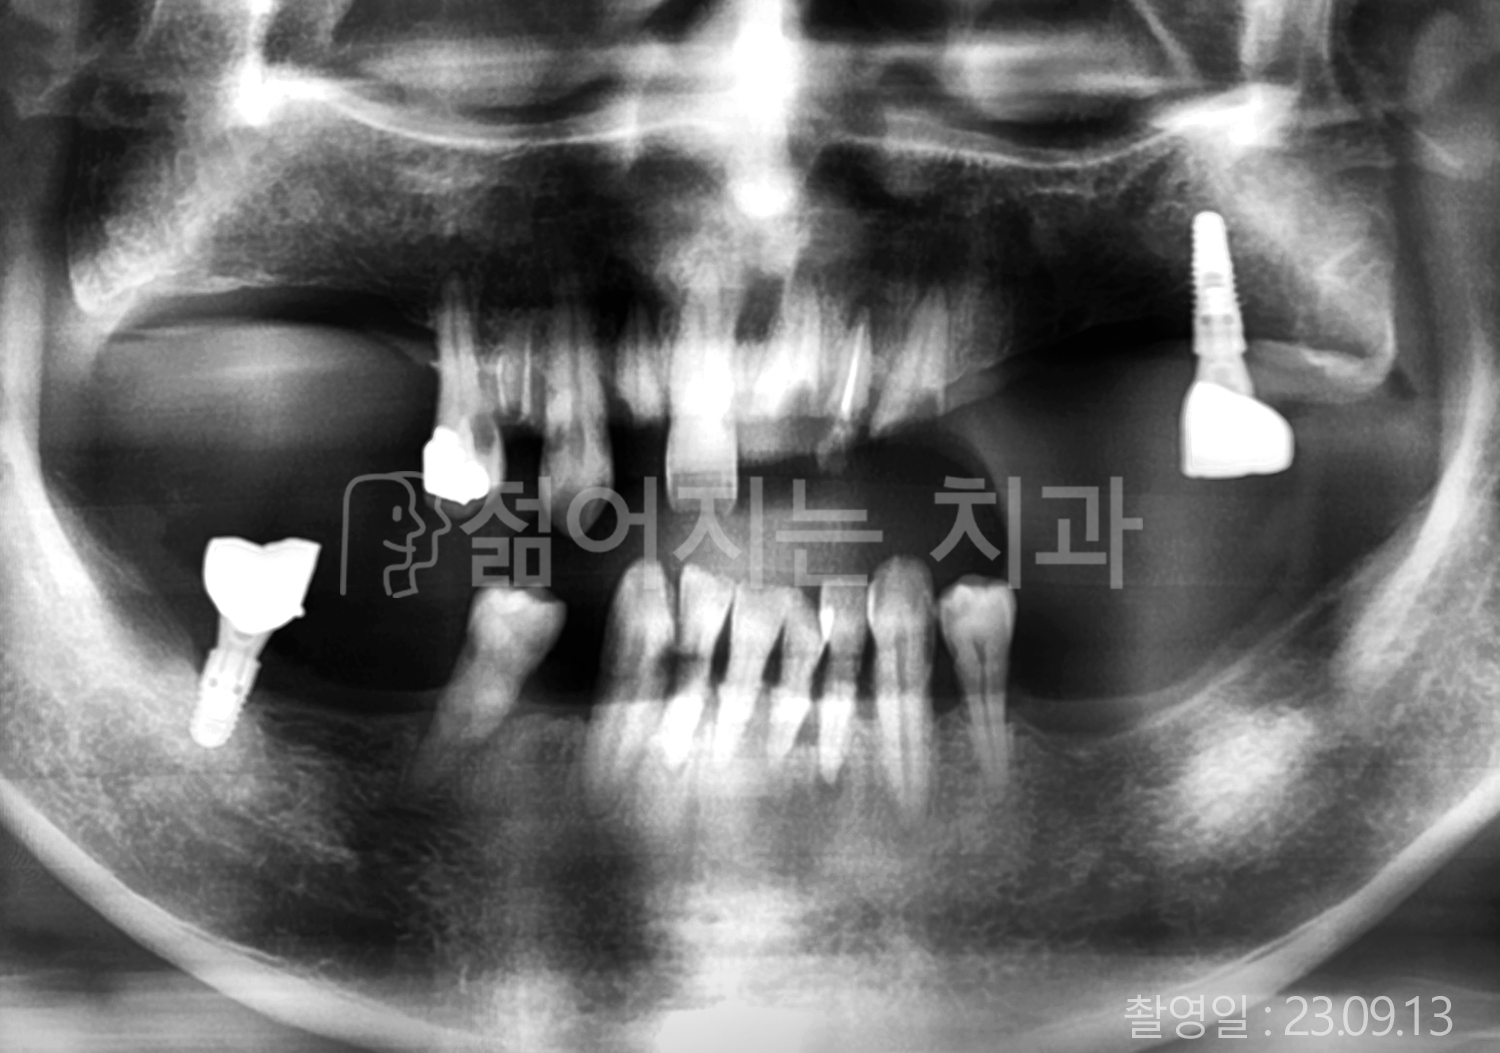

• 70대 고혈압, 고지혈증 전체치아 10개 이상 임플란트

• 60대 당뇨, 간염 전체치아 10개 이상 임플란트

• 80대 골다골증 전체치아 6개 이상 임플란트

• 70대 고혈압, 당뇨 전체치아 10개 이상 임플란트

• 60대 간 질환 전체치아 10개 이상 임플란트

• 60대 전체치아 10개 이상 임플란트

• 70대 전체치아 10개 이상 임플란트

• 50대 전체치아 10개 이상 임플란트

• 60대 고혈압, 고지혈증 전체치아 10개 이상 임플란트

• 40대 고지혈증, 뇌혈관 질환 전체치아 10개 이상 임플란트